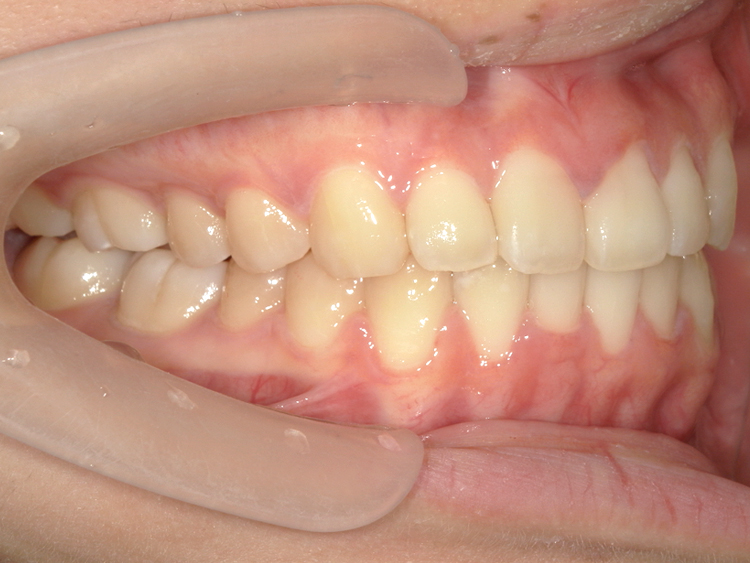

症例4

Before

After

| 主訴 | 上下前歯のがたつき |

|---|---|

| 年齢 | --- |

| 治療 期間 |

約9ヶ月 |

| 治療 内容 |

インビザラインiGoで上下顎の治療。 |

| 治療費 | ¥550,000(税込)/調整料含む |

| 治療のリスク | 矯正終了後は、リテーナーを指示通りに使用し、歯の後戻りを防ぐ必要があります。 |